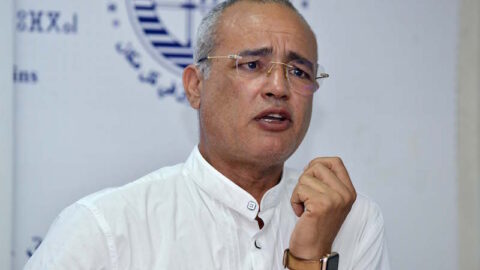

وقال الأستاذ بالجامعة تشو مين شنغ، إن طرق العلاج الحالية لا تؤدي إلا إلى تخفيف الأعراض الالتهابية بدلا من توفير علاج كامل، وذلك بسبب عدم وضوح آليات التسبب في المرض، حتى أن بعض الحالات الشديدة تتطلب استئصال القولون، وهو ما ينطوي على آثار جانبية كبيرة ومعدلات عالية من تكرار الإصابة.

وفي مجموعة من 79 مريضا صينيا، كانت نتائج اختبارات البراز أكثر من 70 في المائة إيجابية لـ “إم تي بي”. وقال جيانغ تشي هوي، المؤلف الأول للدراسة إنه “على عكس الأنواع الأخرى من سلالات بكتيريا الأيروموناس، تملك “إم تي بي” قدرة قوية على الاستعمار المعوي”.